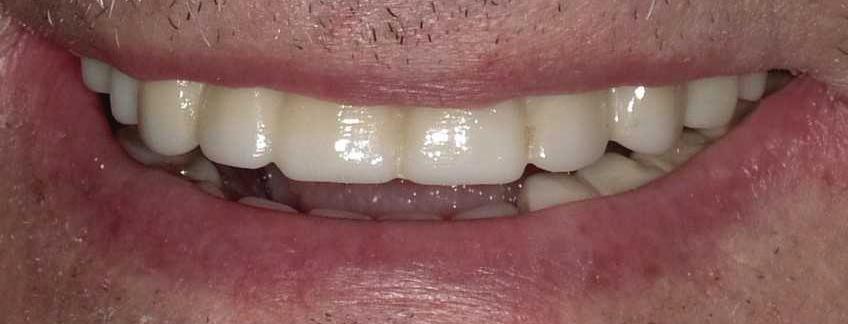

Can just four implants replace all of the teeth on the top or the bottom of your mouth? Thanks to advances in dental implant technology, that answer is a resounding yes.

Tooth loss is extremely common among adults, especially as we age. Rather than living with the discomfort and hassles of dentures, many people are opting for what is called “all-onfour” dental implant restoration.

An implant is a small titanium screw

that fits inside your jawbone and replaces the root-part of a missing tooth. Minor surgery is required to insert the implants. Once the implant is in place, a crown is attached to give you a highly realisticlooking and functional prosthetic tooth.

You do not need a dental implant for each and every one of your missing teeth. All you need is four precisely placed implants on the top of your mouth, and four on the bottom, to restore your full smile. That’s the beauty of the all-on-four. And because the implant is made of titanium, it has the unique ability to fuse to living bone and function as part of it. So eventually, the dental implant becomes part of the jawbone and serves as a strong, longlasting foundation for your new teeth.

Besides ensuring that your implants are permanently fixed in place, this bone fusion has another important benefit: it prevents future bone loss in the jaw. This helps to maintain a more youthful facial structure – and better oral health. But perhaps the biggest

Please see “All-On-Four,” page 61